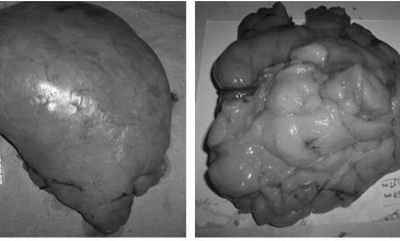

Sau ca phẫu thuật, khối u mỡ được tách bỏ có kích thước 17x22cm, nặng 1,5kg, có vỏ bọc mỏng. Kết quả mô bệnh học cũng khẳng định đây là một u mỡ lành tính. Hiện bệnh nhân đã ra viện và tình trạng sức khoẻ đã ổn định.